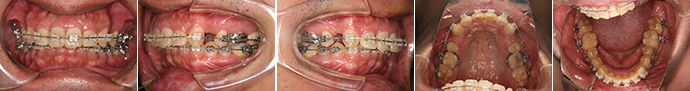

| 主訴 | 上の前歯が出ている、下の前歯がデコボコ |

| 年齢・性別 | 26歳 / 女性 |

| 治療方針 | 顎関節に少し問題があるAngleⅠ級上下顎前突。患者の希望もあり、できるだけ前歯を後退して口元の突出感の改善を行う。 |

| 抜歯部位 | 小臼歯4本抜歯 |

| 使用装置 | ホールディングアーチ、マルチブラケット装置 |

| 治療期間 | 26か月 |

| リテーナー | 上顎インビジブル、下顎スプリングリテーナー |

| 費用 | 825,000円(税別) |